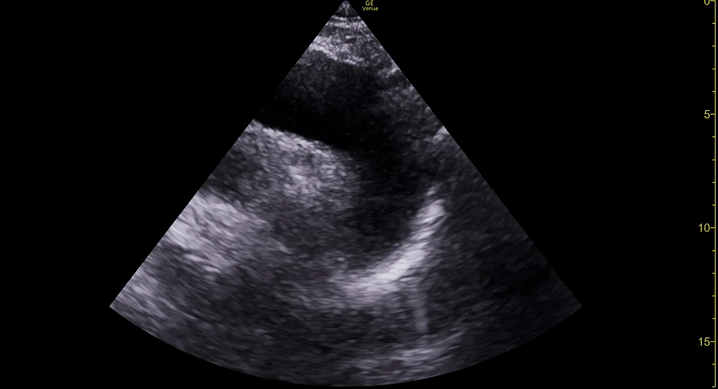

Exit: is there acute aortic root pathology?

Thoracic Aortic dissection is a time-dependent and deadly pathology that can occur silently or be masked by a variety of clinical presentations. While angio-CT remains the gold standard for diagnosis, US may be performed quicker and at the bedside. In the visible portion of the aortic root, the US findings can include intimal flap, aortic valve insufficiency, retrograde aortic flow, or rupture into the pericardium with pericardial effusion and tamponade. Alternatively, dilation of the aortic root is characteristic of a thoracic aortic aneurysm.

Importantly, remember that thoracic aortic dilation or intimal flap may occur distal to the aortic root, where an US scan is usually blind. Hence, the absence of dilation or flap does not rule out aortic disease.

THE VIEWS

The PLAX view is best for exploring the aortic root. If performed by an experienced operator, aortic root measurements in this window correlate well with angio-CT measurements.

The Aortic root size varies with age and gender and should be measured at its widest point, perpendicular to its long axis. In general, a root > 4 cm should be considered borderline and enough to warrant a formal study.

Alternatively, the aortic root size can be estimated by the rule of thirds, where in the PLAx view the size of the RV, AoR, and LA should be roughly 1:1:1.

AORTIC DISSECTION

In both of these views, US may detect an intimal flap seen as a hyperechoic linear structure within the aortic lumen that moves with each heartbeat. The visualization of a flap carries a high specificity and should prompt immediate consultation with cardiothoracic surgery; however, ultrasound sensitivity for intimal flap is significantly low, and its absence does not rule out aortic dissection.